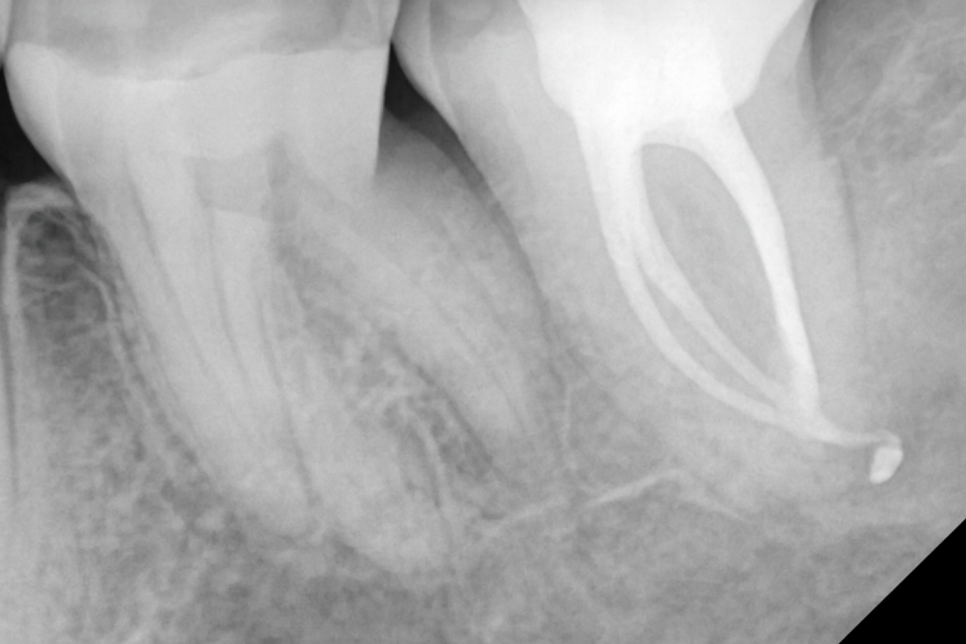

이후 감염이 해소되는 양상이 관찰되면

당산동 치과 에서 준비한 예시 사진처럼

내부를 생체친화적인 재료로 충전하게 되는데,

이때도 신중을 기여해야 됩니다.

밀봉이 잘 되어야 추후 세균 감염이 다시 생겨날

우려가 적어지기 때문에

충전재를 사용하여 밀폐를 얻어내는데 집중합니다.